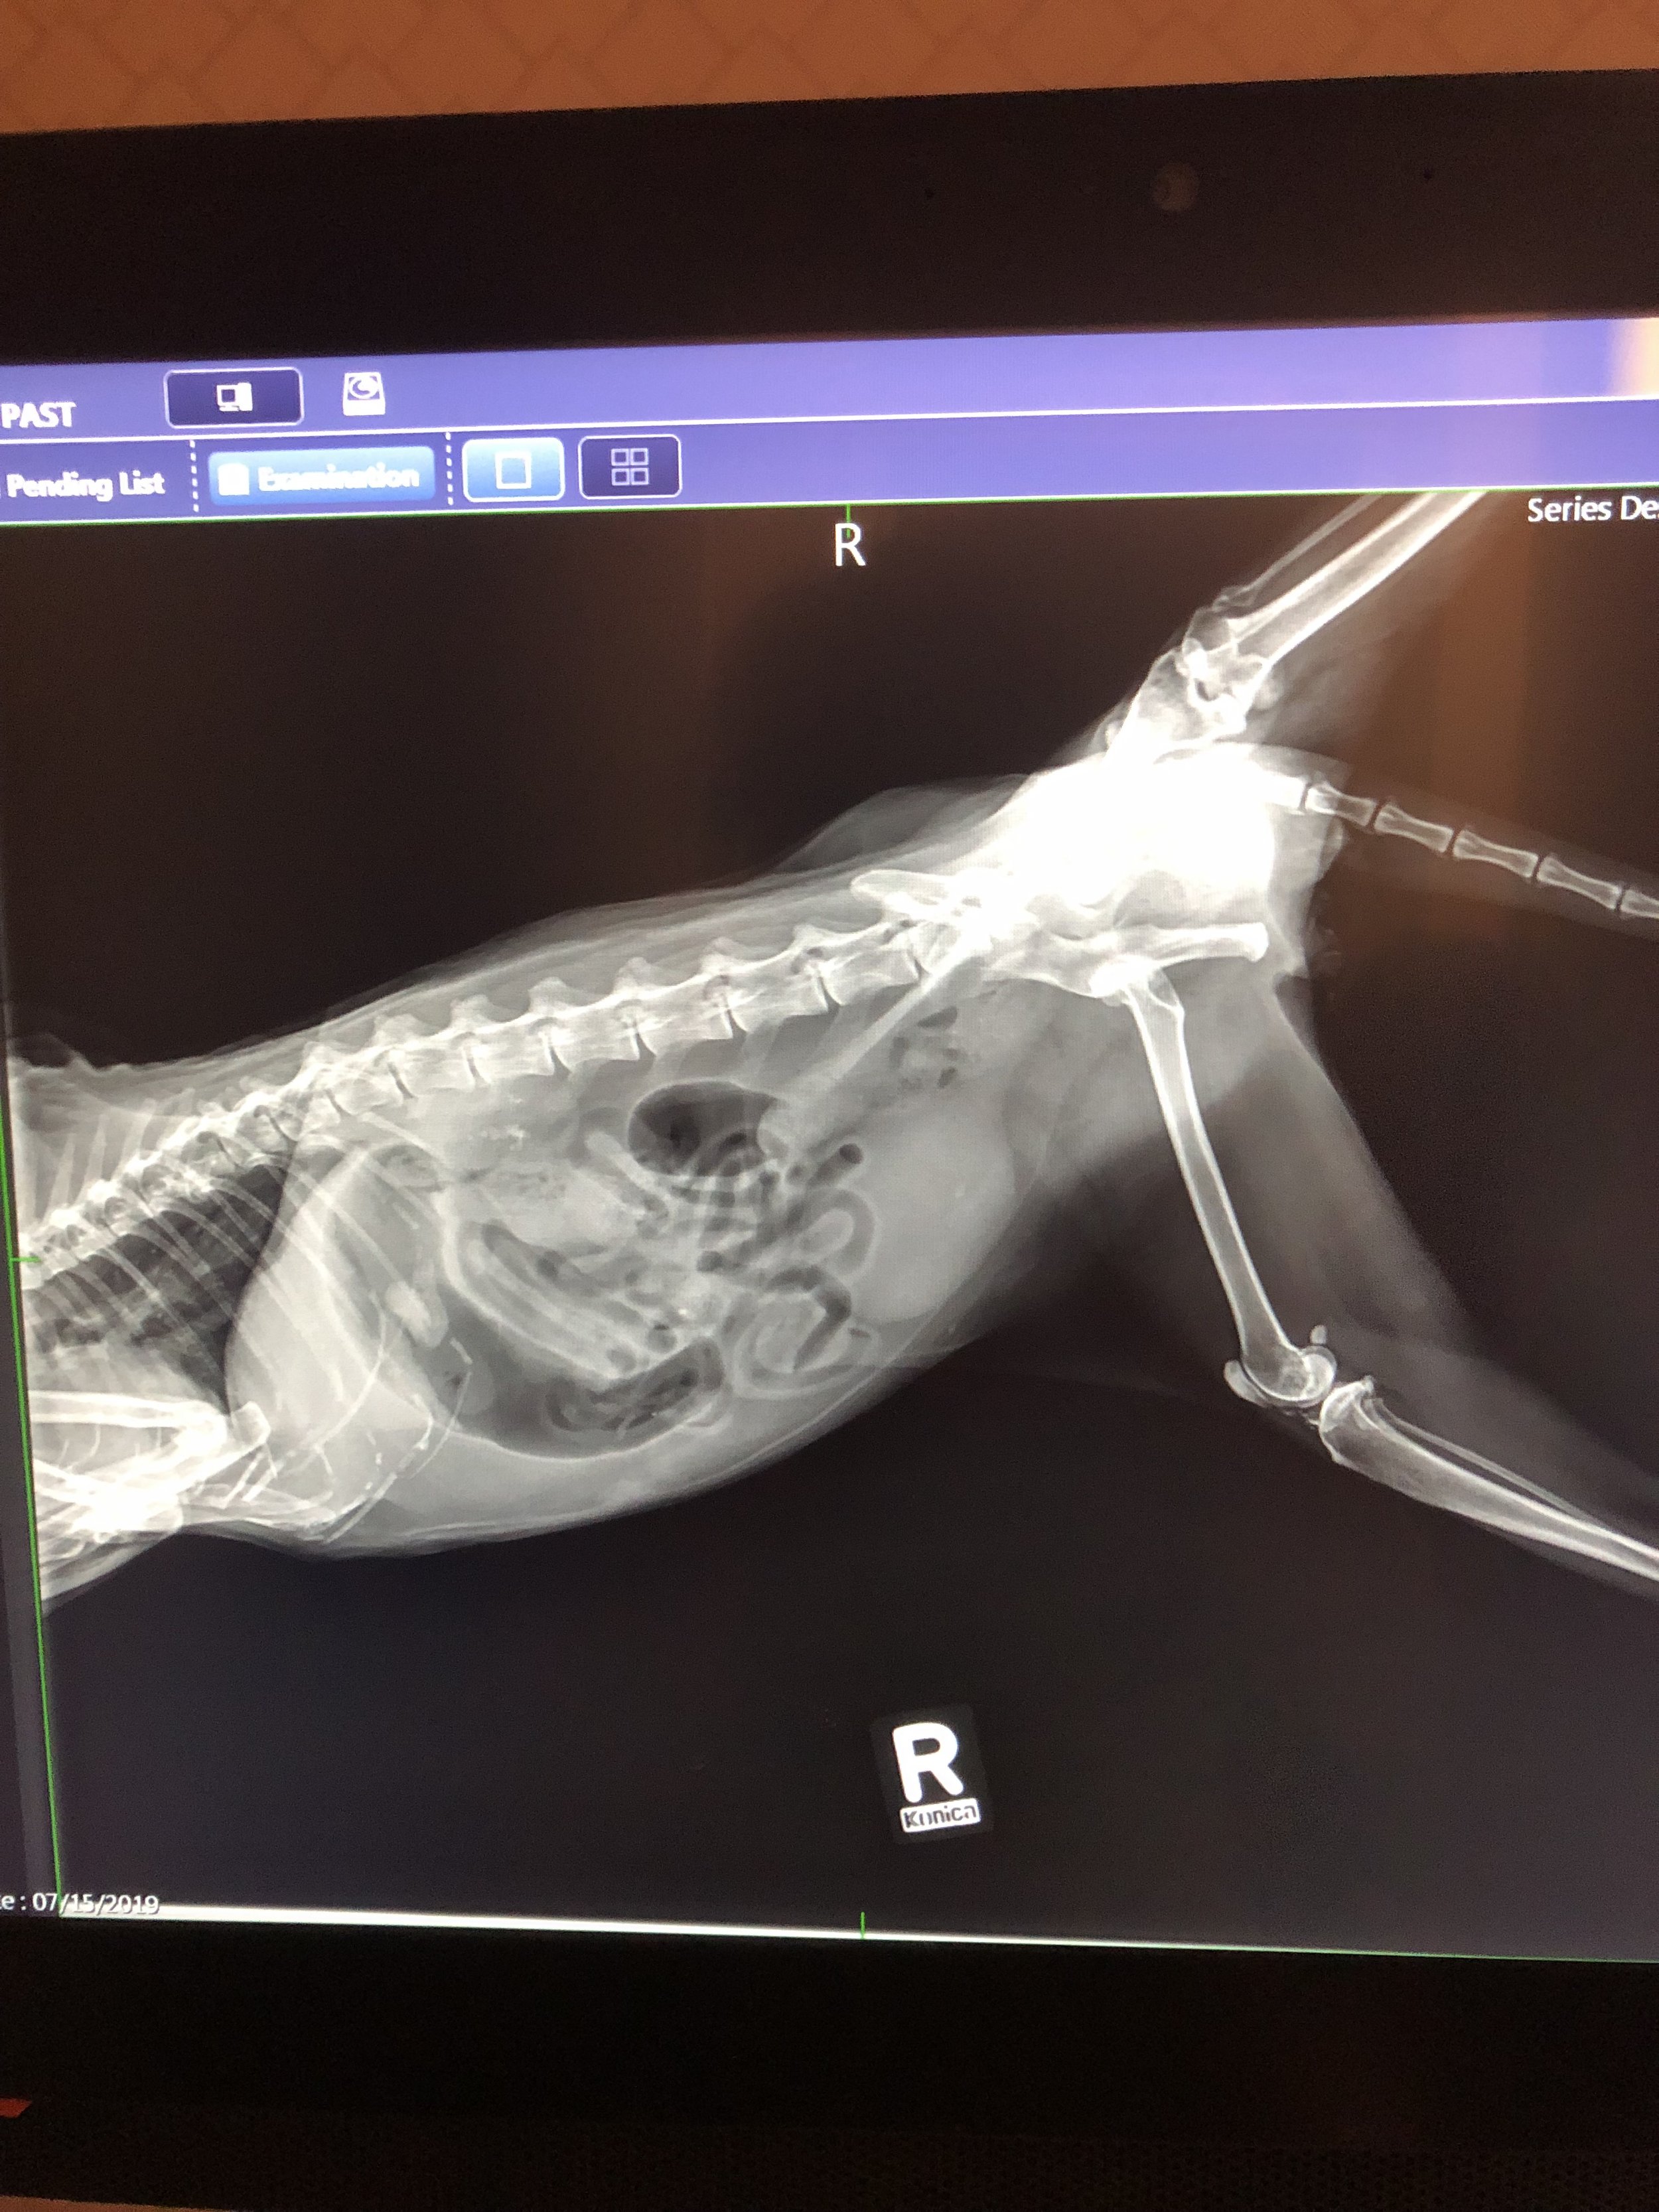

At Silvercreek Animal Hospital, we use digital radiography (X-rays) to help diagnose a wide range of health conditions quickly and safely. X-rays give us a detailed view of your pet’s bones, joints, and internal organs—allowing us to detect issues that can’t be seen during a physical exam alone.

- Broken bones or fractures

- Arthritis and joint problems

- Tumors or abnormal growths

- Heart or lung conditions

- Bladder stones

- Foreign objects